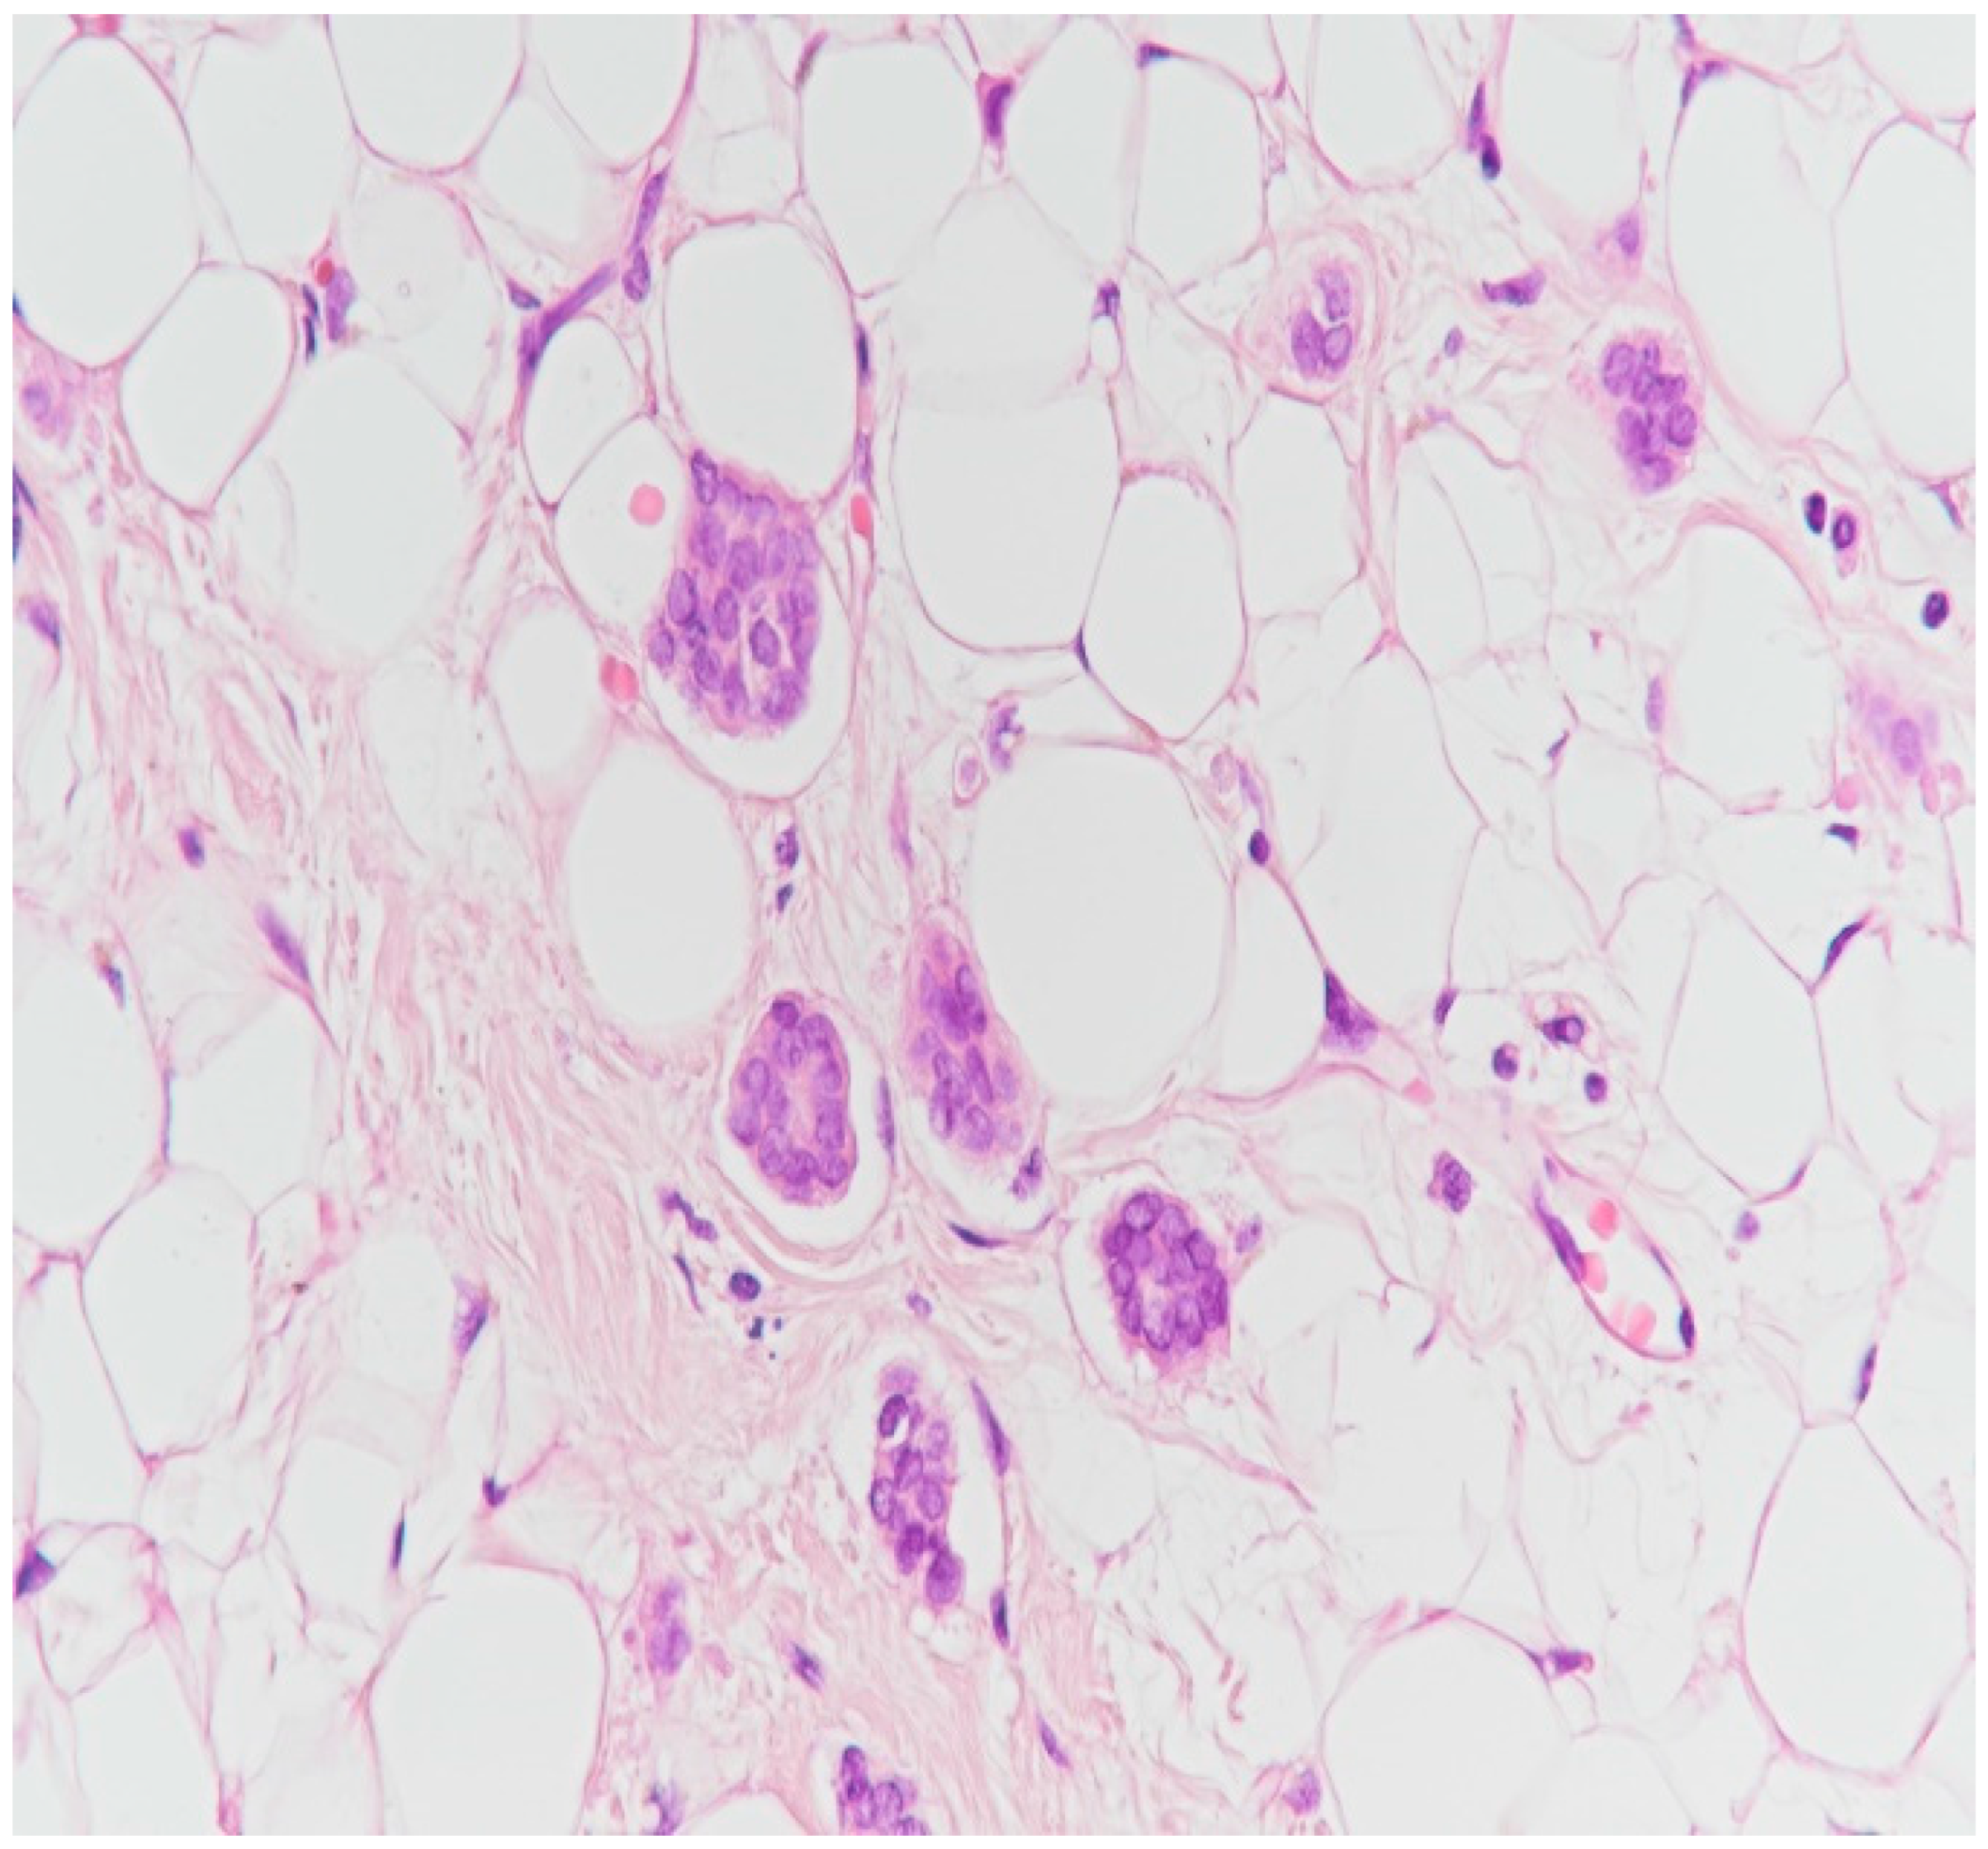

2. Case Presentation